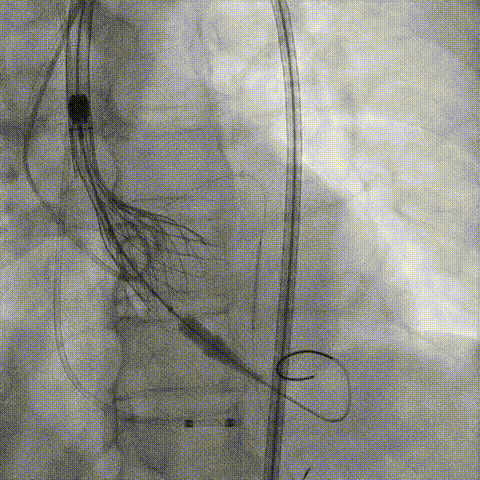

第一次释放

再次评估左冠开口,考虑调整瓣膜深度

回收后调整深度,再次释放

评估左冠开口

左冠开口切线位造影

决定左冠烟囱支架保护冠脉

调整支架位置

释放冠脉支架

释放瓣膜

造影评估

支架内后扩张

冠脉造影

根部造影